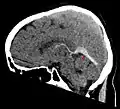

Синус-тромбоз при нативной компьютерной томографии (сагиттальная реконструкция)